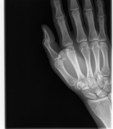

Broken Hand

This was just a hairline fracture that I managed to get from a soccer game. I thought it was pretty cool that I was given all of the digital copies.

Broken Hand (264473)